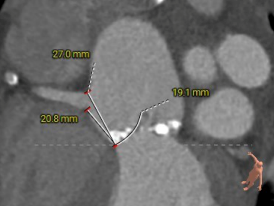

CT测量

主动脉根部CT测量

瓣环周长:90.3mm

LVOT周长:97.1mm

瓣环上4mm:82.7mm

瓣环上6mm:85.6mm

左冠开口高度:21.4mm

右冠开口高度:16.3mm

左窦瓣叶长度:20.8mm

右窦瓣叶长度:19.1mm

STJ周长:129.8mm

升主动脉周长:157.5mm

法氏窦

周长:133.9mm;左冠状窦直径:45.4mm;无冠状窦直径:31.8mm

主动脉瓣钙化积分:787mm2